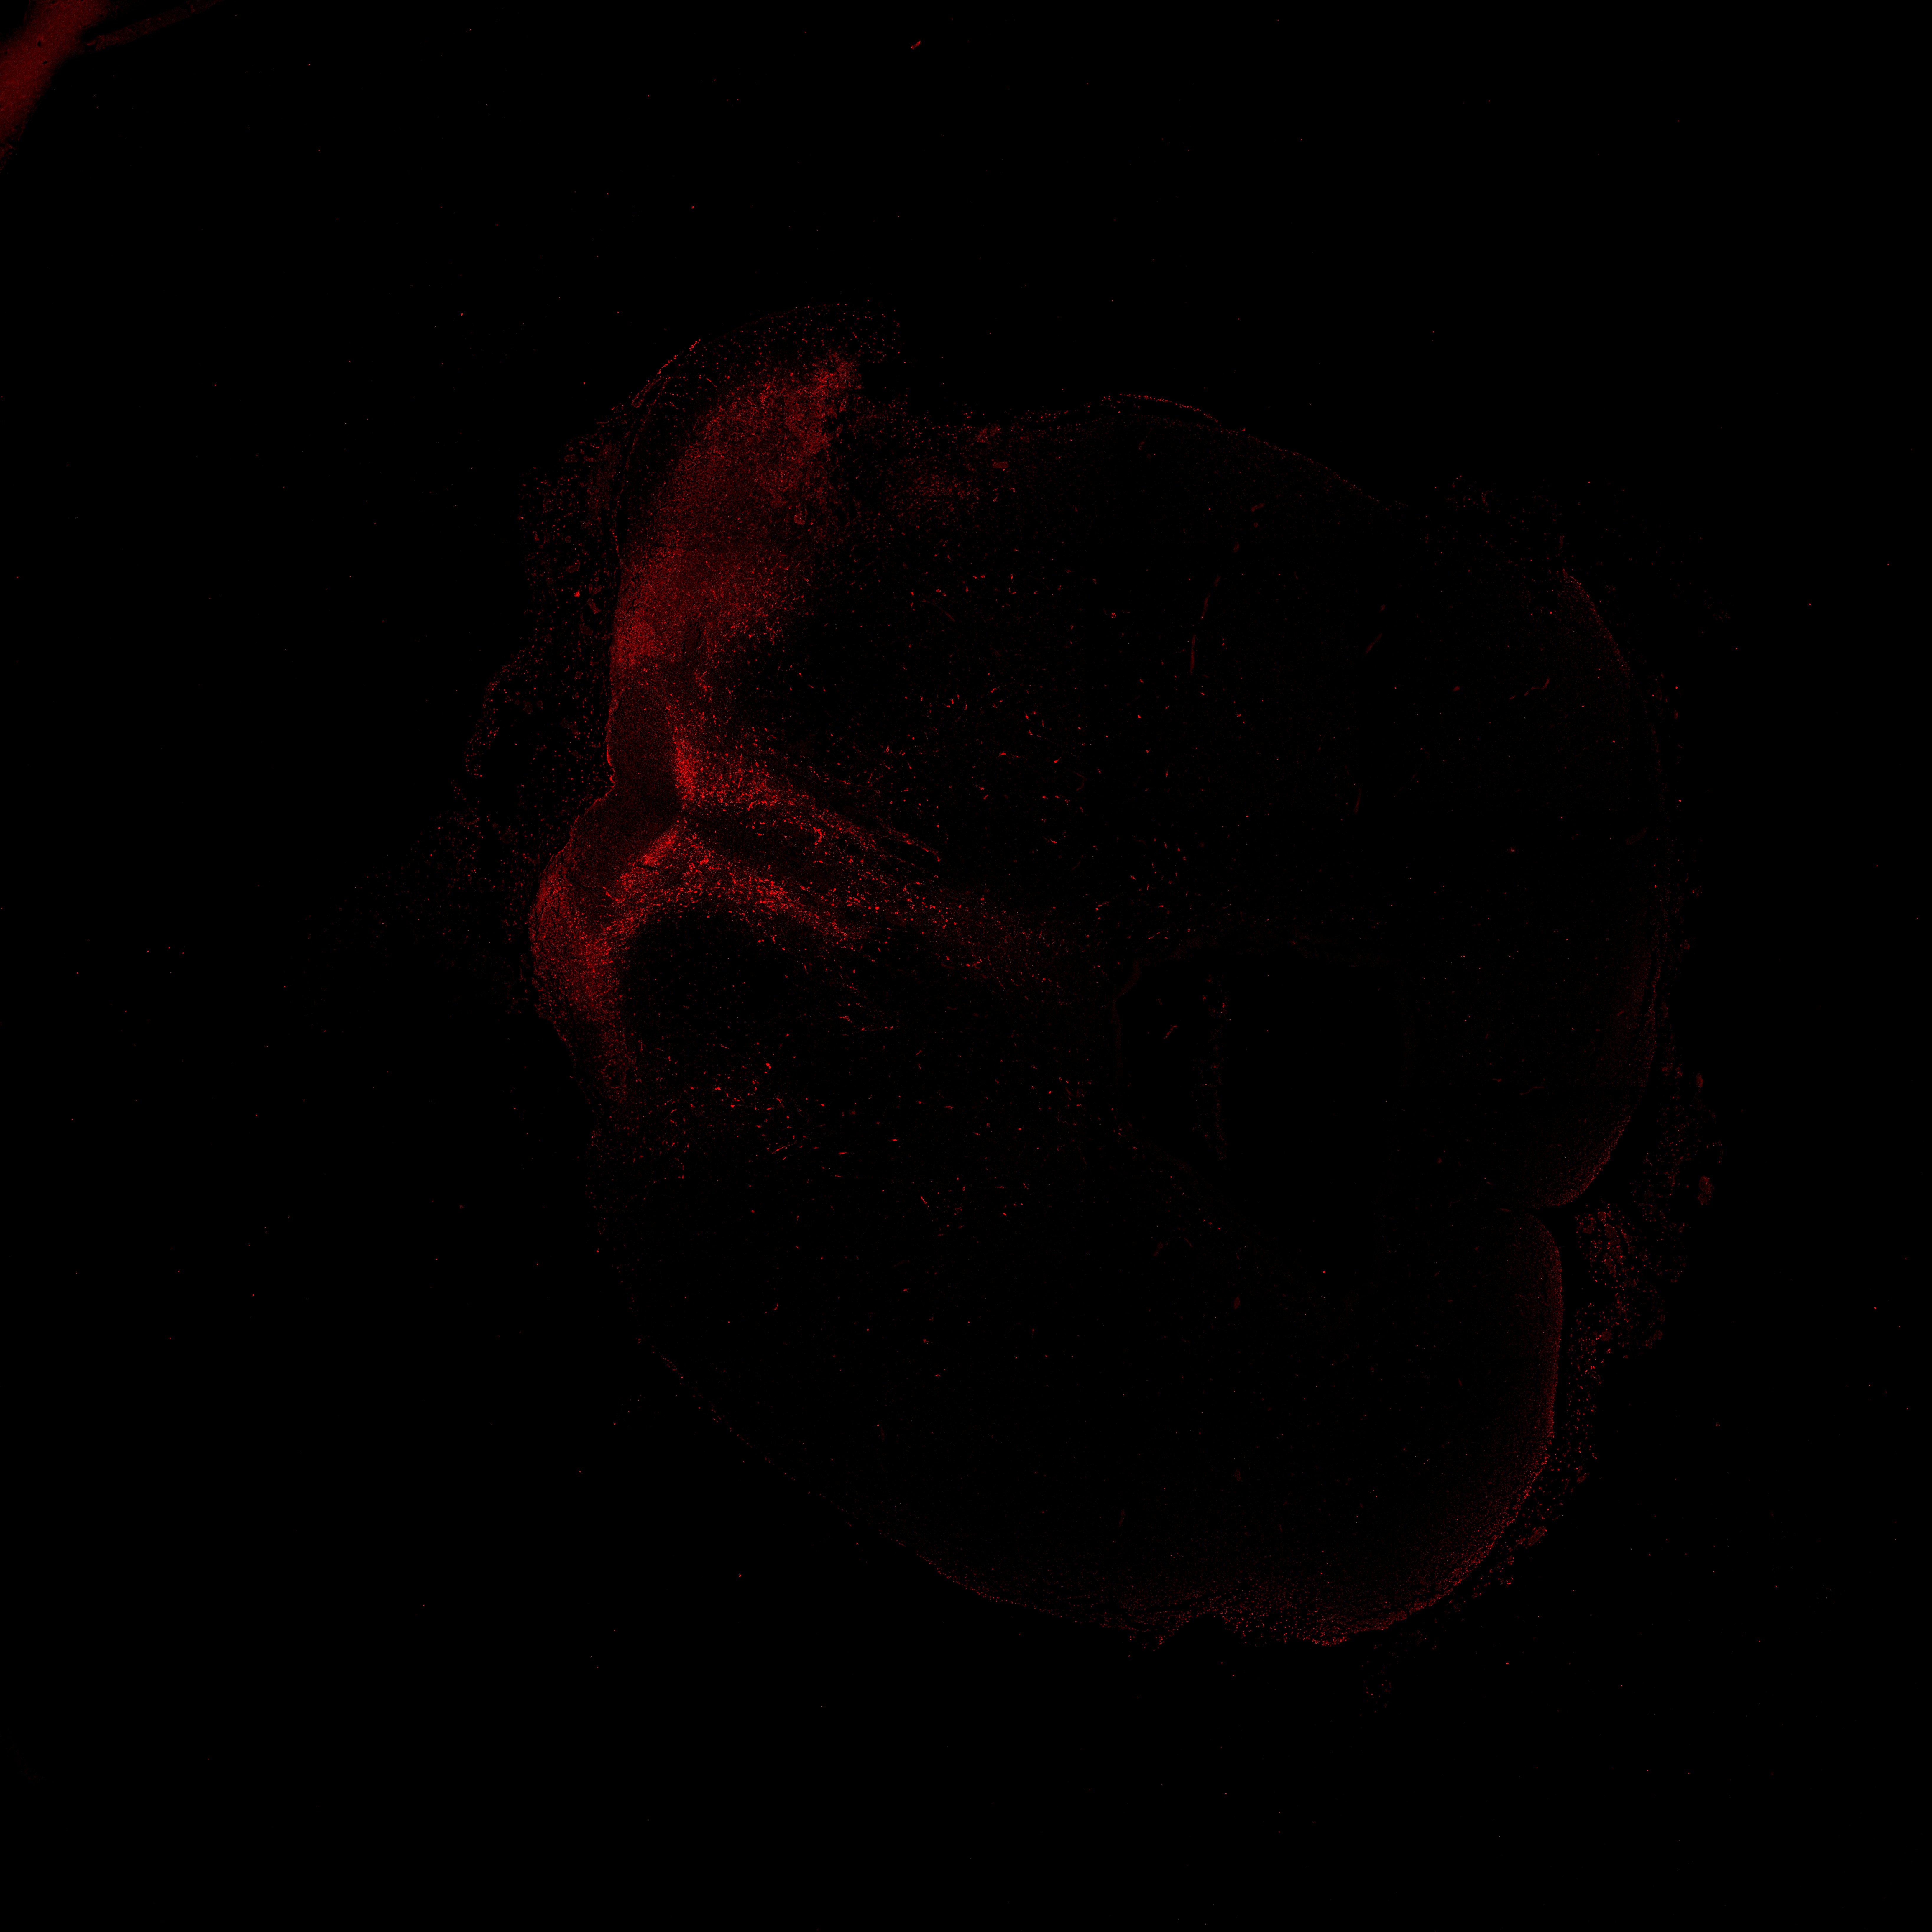

An anatomical analysis of the developing human midbrain from 6 post-conceptional weeks (PCW) to 22 PCW reveals increased tissue complexity, characterized by the emergence of dopaminergic nuclei, as highlighted by immunofluorescence analysis for tyrosine hydroxylase (TH).

TH

7PCW human midbrain